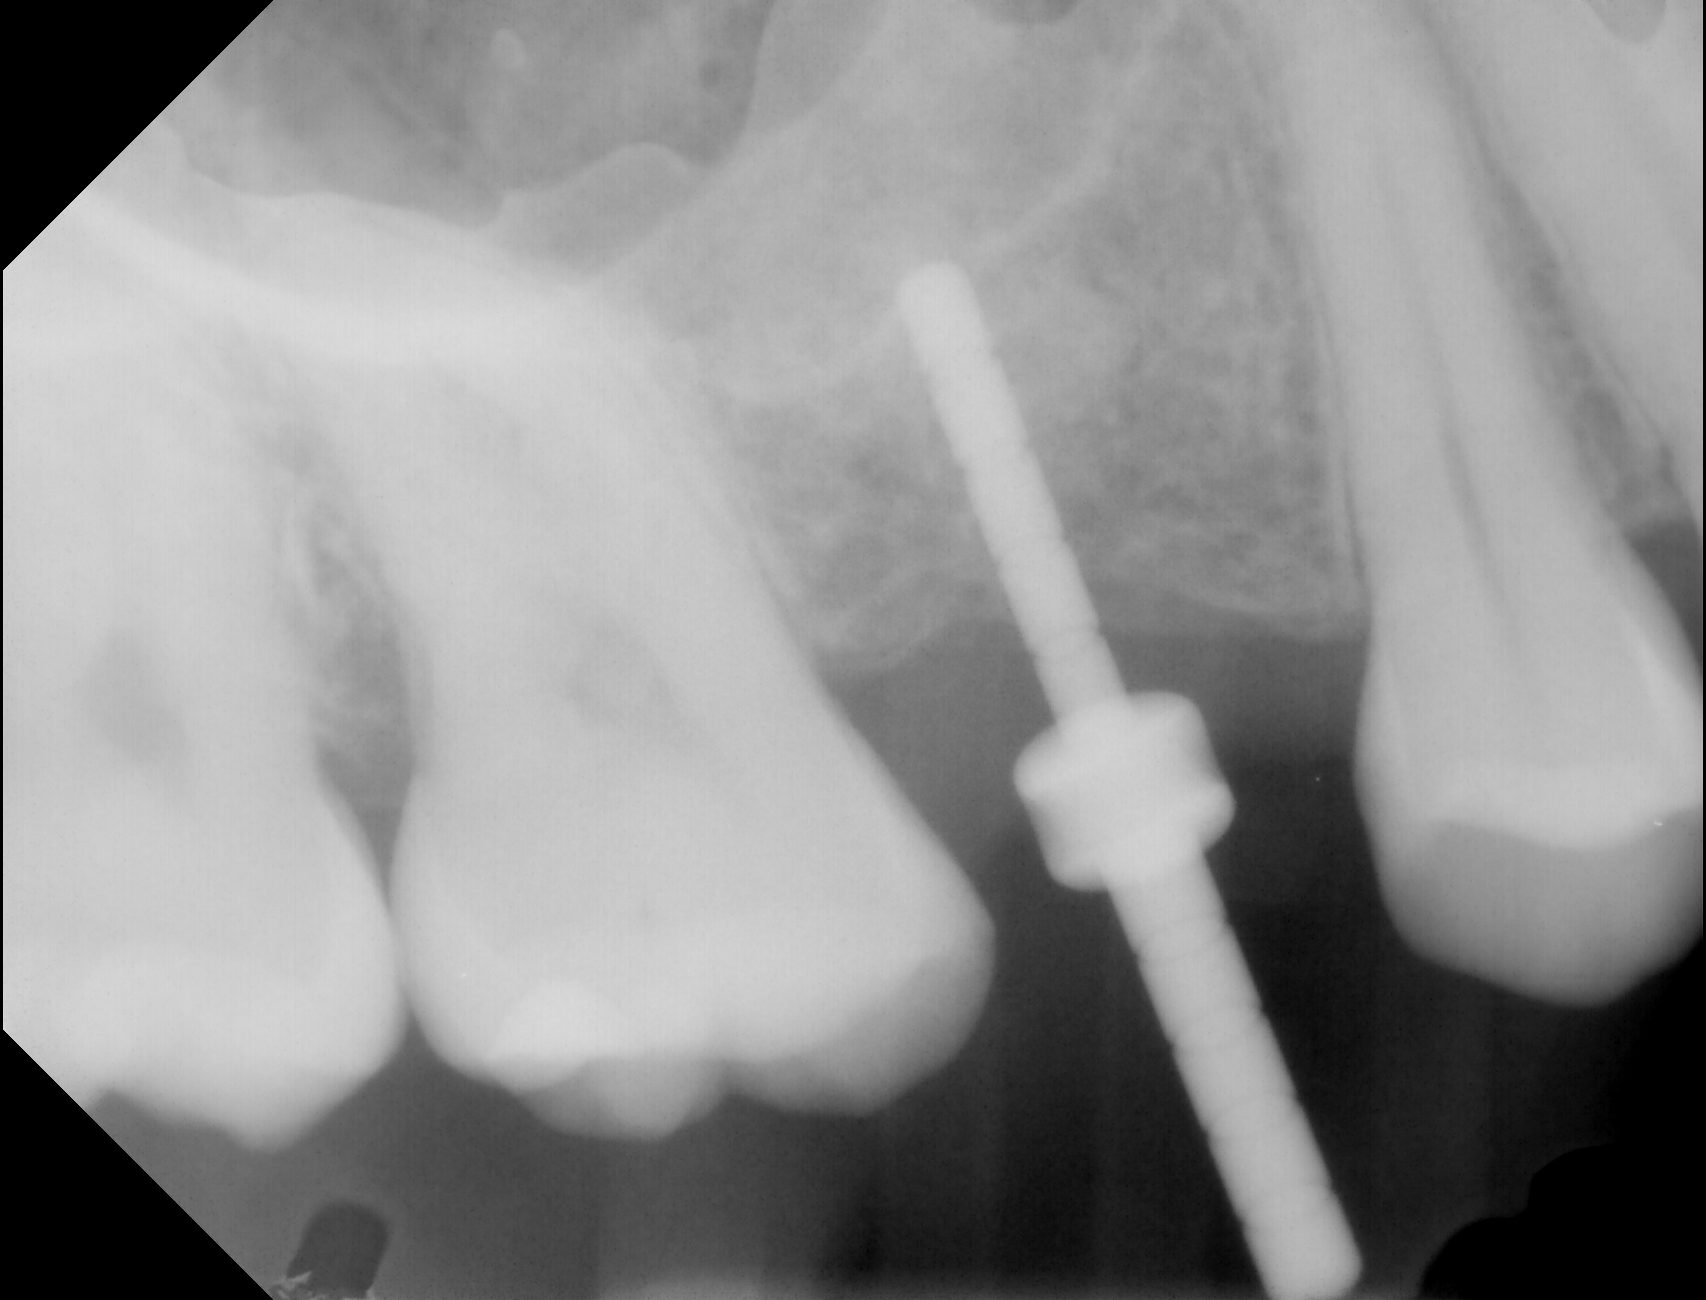

Here are 3 steps of installing implants

Here are 3 steps of installing implants

Here are 3 steps of installing implants

Here are 3 steps of installing implants

Here are 3 steps of installing implants